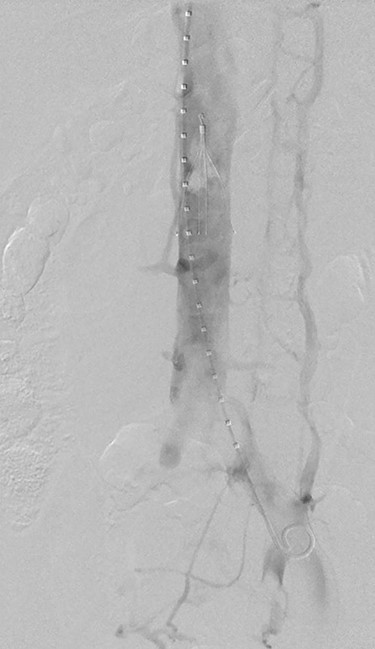

(A) Venogram illustrating patent IVC and renal vein position. (B) Post-thrombectomy venogram showing fenestrated left common iliac vein. (C) Venogram illustrating patent popliteal vein via small saphenous vein access.

After ultrasound-guided right common femoral vein access, venogram illustrated both the position of the renal veins and a patent inferior vena cava (IVC) (Fig. 2A). An infrarenal IVC filter was deployed (Celect Platinum Vena Cava Filter by COOK Medical) (Fig. 2B). A diagnostic venogram was performed via the left short saphenous vein (Fig. 2C), and this confirmed patency of the common femoral vein, femoral vein and the popliteal vein. Ultrasound was again utilized to puncture the left great saphenous vein proximally, with insertion of a 6-Fr sheath with a glide and Bern catheter used to cross the occluded common iliac vein and external iliac vein. An Angiojet thrombectomy catheter (by Boston Scientific) was placed within the thrombus, and a total of 19.4 mg of alteplase was infiltrated. After waiting 30 minutes for the alteplase to diffuse, a venogram was performed that demonstrated some resolution of the thrombus. Suction thrombectomy was then performed. Completion venogram illustrated a fenestrated left common iliac vein with resolution of the DVT (Fig. 2B). A balloon was inflated at the level of the fenestration to confirm separate channels. The irritation of the access vein’s intima for the SVT ablation in conjunction with the fenestrated common iliac vein was the suspected cause of the patient’s DVT. The patient was changed to therapeutic low-molecular-weight heparin post-operatively.